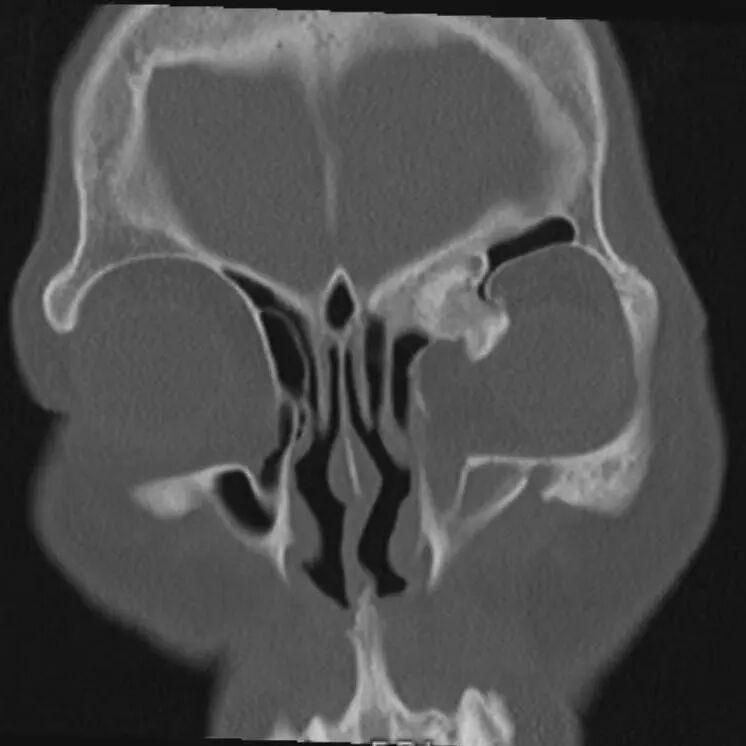

术前CT影像

患者最终来到我院耳鼻咽喉头颈外科寻求转机,经过更为精细的检查,发现这并非简单的眼眶肿物,而是起源于鼻窦、突入眼眶并与颅底紧密连接的一个横跨鼻、眼、颅底三个关键区域的“跨界”骨性肿瘤,稍有不慎,就可能造成颅底损伤,导致脑脊液鼻漏,手术难度与风险陡然升级。